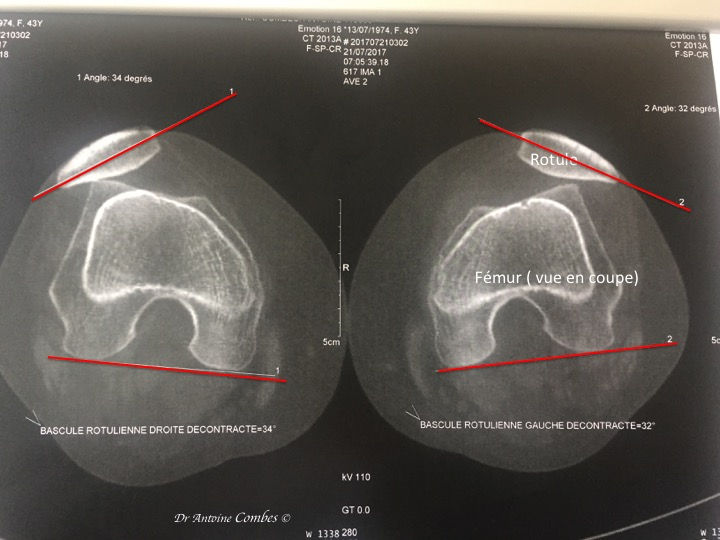

Bascule rotulienne

Grand axe de la rotule (G) et Condyles (C)